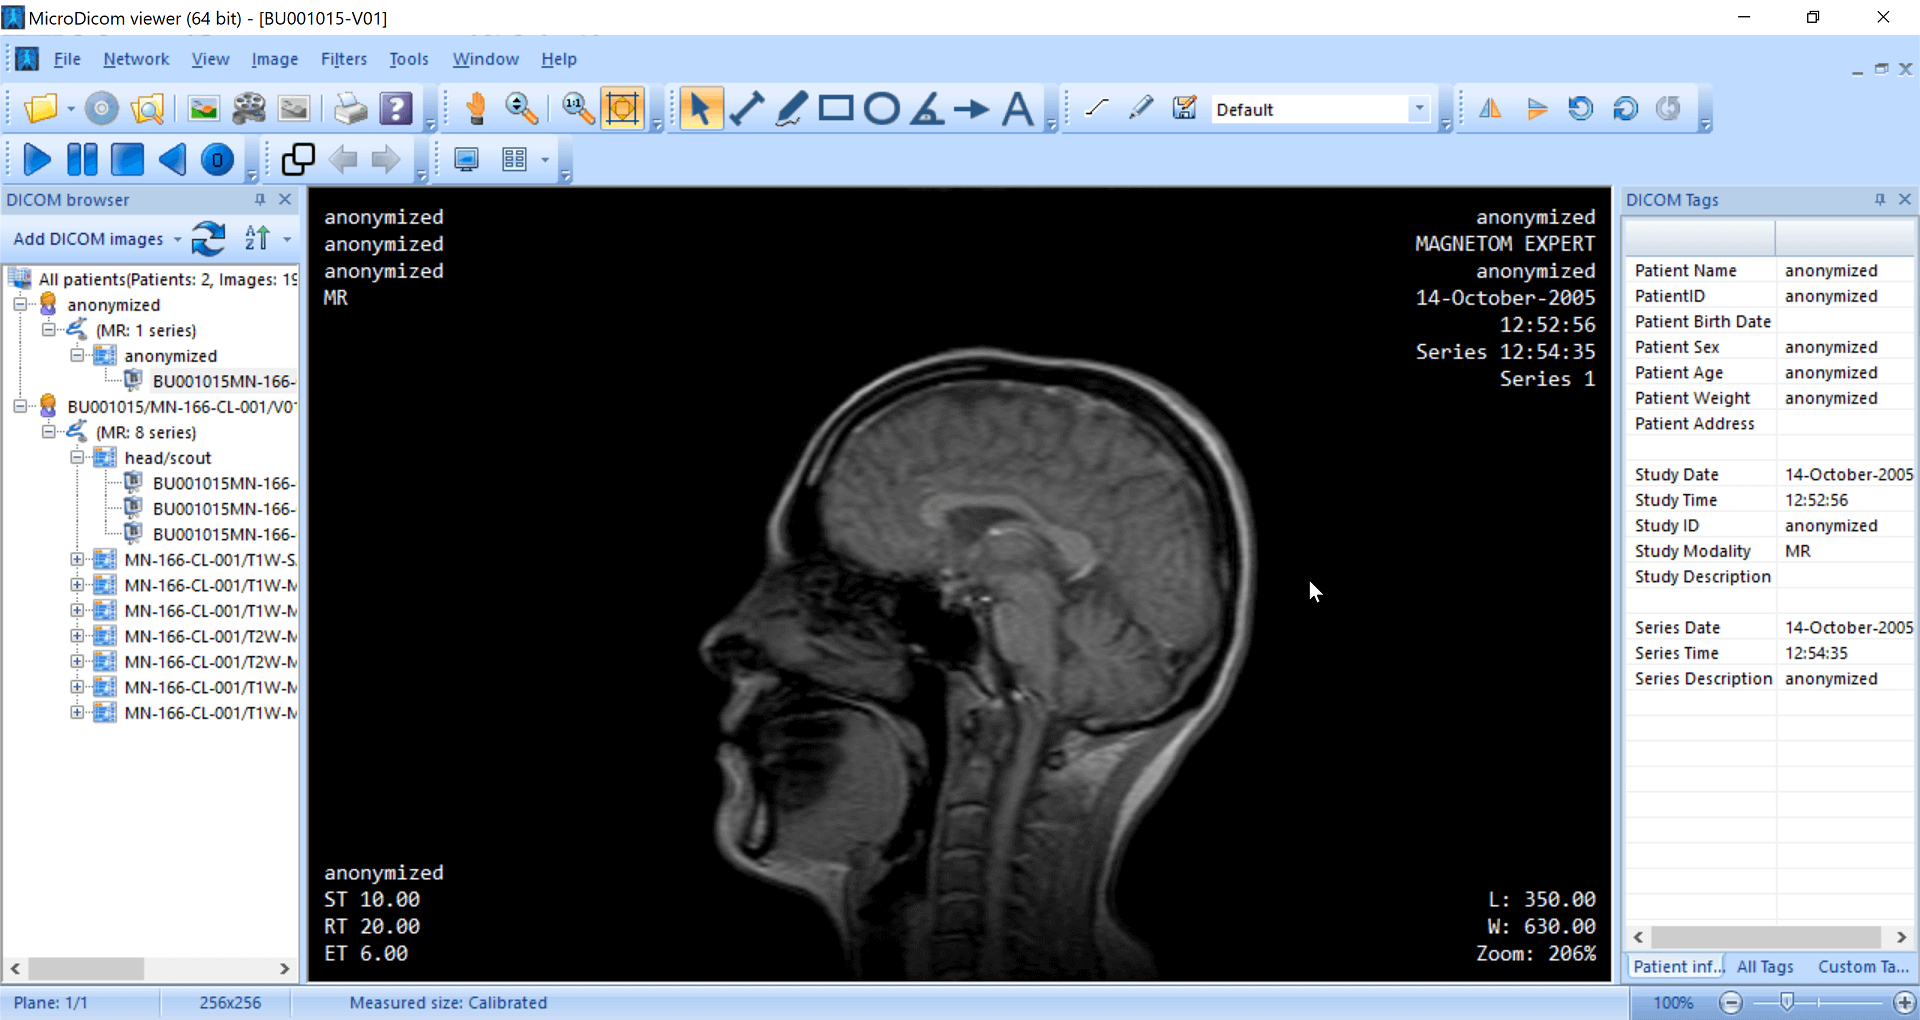

The application allows both viewing and processing of DICOM images. It can generate structured reports, and allows basic measurements, annotations, and zooming in for images. MicroDicom does not offer advanced features such as MPR and volume rendering. It can be downloaded as a potable zip file that does not require installation. This allows it to be used on any device that has a Windows OS.

| 6. | MicroDicom | Windows | Not available | N | N | N | Picture (JPEG, PNG) and movie file (AVI) formats | 14 MB | N.A. | Freeware; no CE mark or FDA approval |